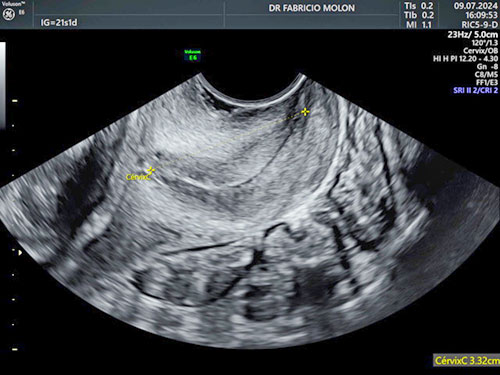

US transvaginal para Rastreamento de Risco de parto prematuro (medida do colo uterino)

É realizada entre o 20 e 24 semanas - normalmente junto com a US morfológica do 2º trimestre.

Este exame é importante para avaliação da possibilidade de um parto prematuro, muitas vezes, fazendo com que se consiga evitar que o bebê nasça antes da hora.

Nele é feito a medida do colo uterino através da ultrassonografia.